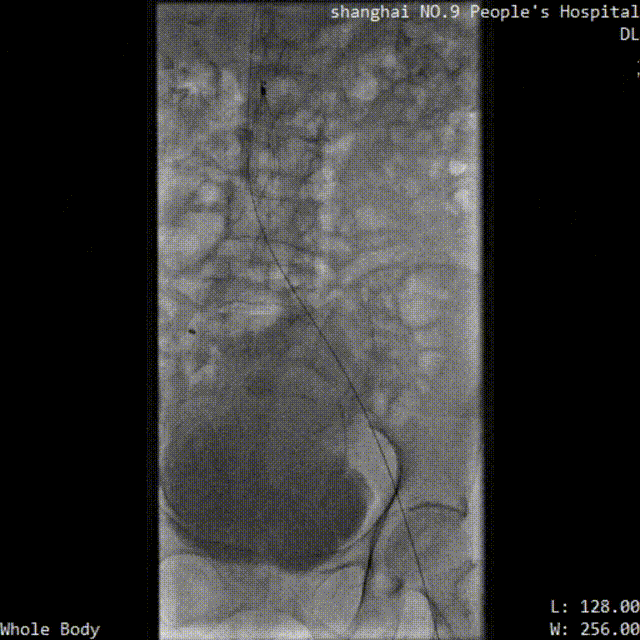

■ LuVoCaptor取栓前后管腔造影對照:

取栓術前管腔造影

取栓術后管腔造影